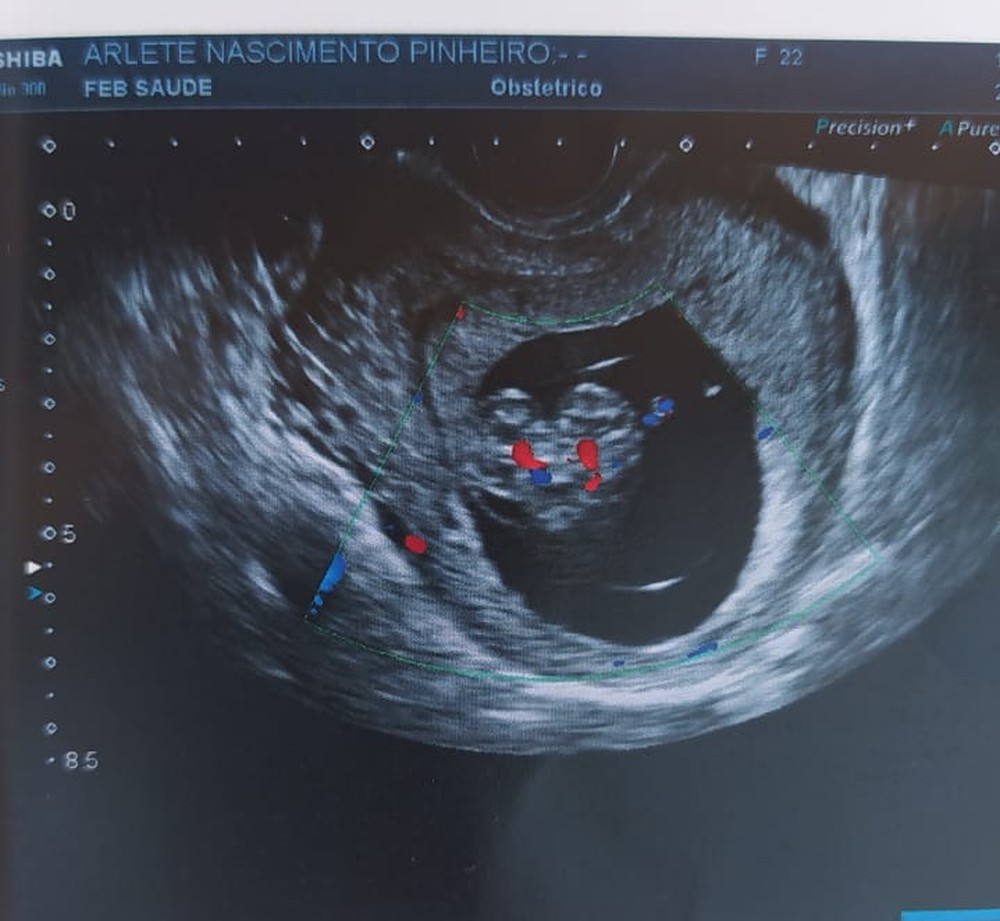

A manicure Arlete do Nascimento Pinheiro, de 22 anos, está grávida de gêmeos siameses. As crianças dividem o mesmo coração, e a jovem, que está no sétimo mês de gestação, relata a apreensão de não saber se os filhos vão sobreviver ao parto. As informações são do portal G1.

Os pais não escolheram os nomes das crianças. Os gêmeos são grudados do tórax ao abdômen e dividem um único coração. Após perceberem a situação dos bebês, os médicos orientaram o casal a não criar expectativas em relação ao nascimento.